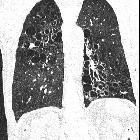

Kartageners

syndrome. Cystic bronchiectasis in both lungs with predominance in lower lobes. Few centrilobular micro nodules representing mucoid impaction with few areas of ground glass opacities are seen in the left lower lobe.

Cystic bronchiectasis is one of the less common morphological forms of bronchiectasis. It may be present on its own or may occur in combination with other forms of bronchiectasis.

It is characterized by saccular dilatation of bronchi that extends to the pleural surfaces. When aggregated these may give a "bunch of grapes" like appearance.